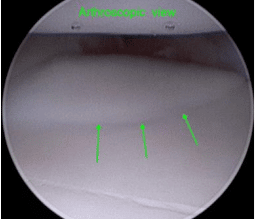

The most common way that we manage a fragmented coronoid process would be to perform a keyhole procedure known as arthroscopy. During this procedure a small camera in inserted into the joint through a small incision in the skin. This allows us to examine the joint, providing more information about the underlying condition. The health of the cartilage can be assessed, which may give an indication about further lameness episodes. Should a fissure or fragment of the coronoid process be present then it is normally removed at this time. If an OCD cartilage flap was present this would also be treated.

The procedure also allows us to decide if additional treatment may be required. Young dogs may benefit from an ulna osteotomy. The ulna is cut below the elbow joint. The aim of this is to improve the congruency of the joint.